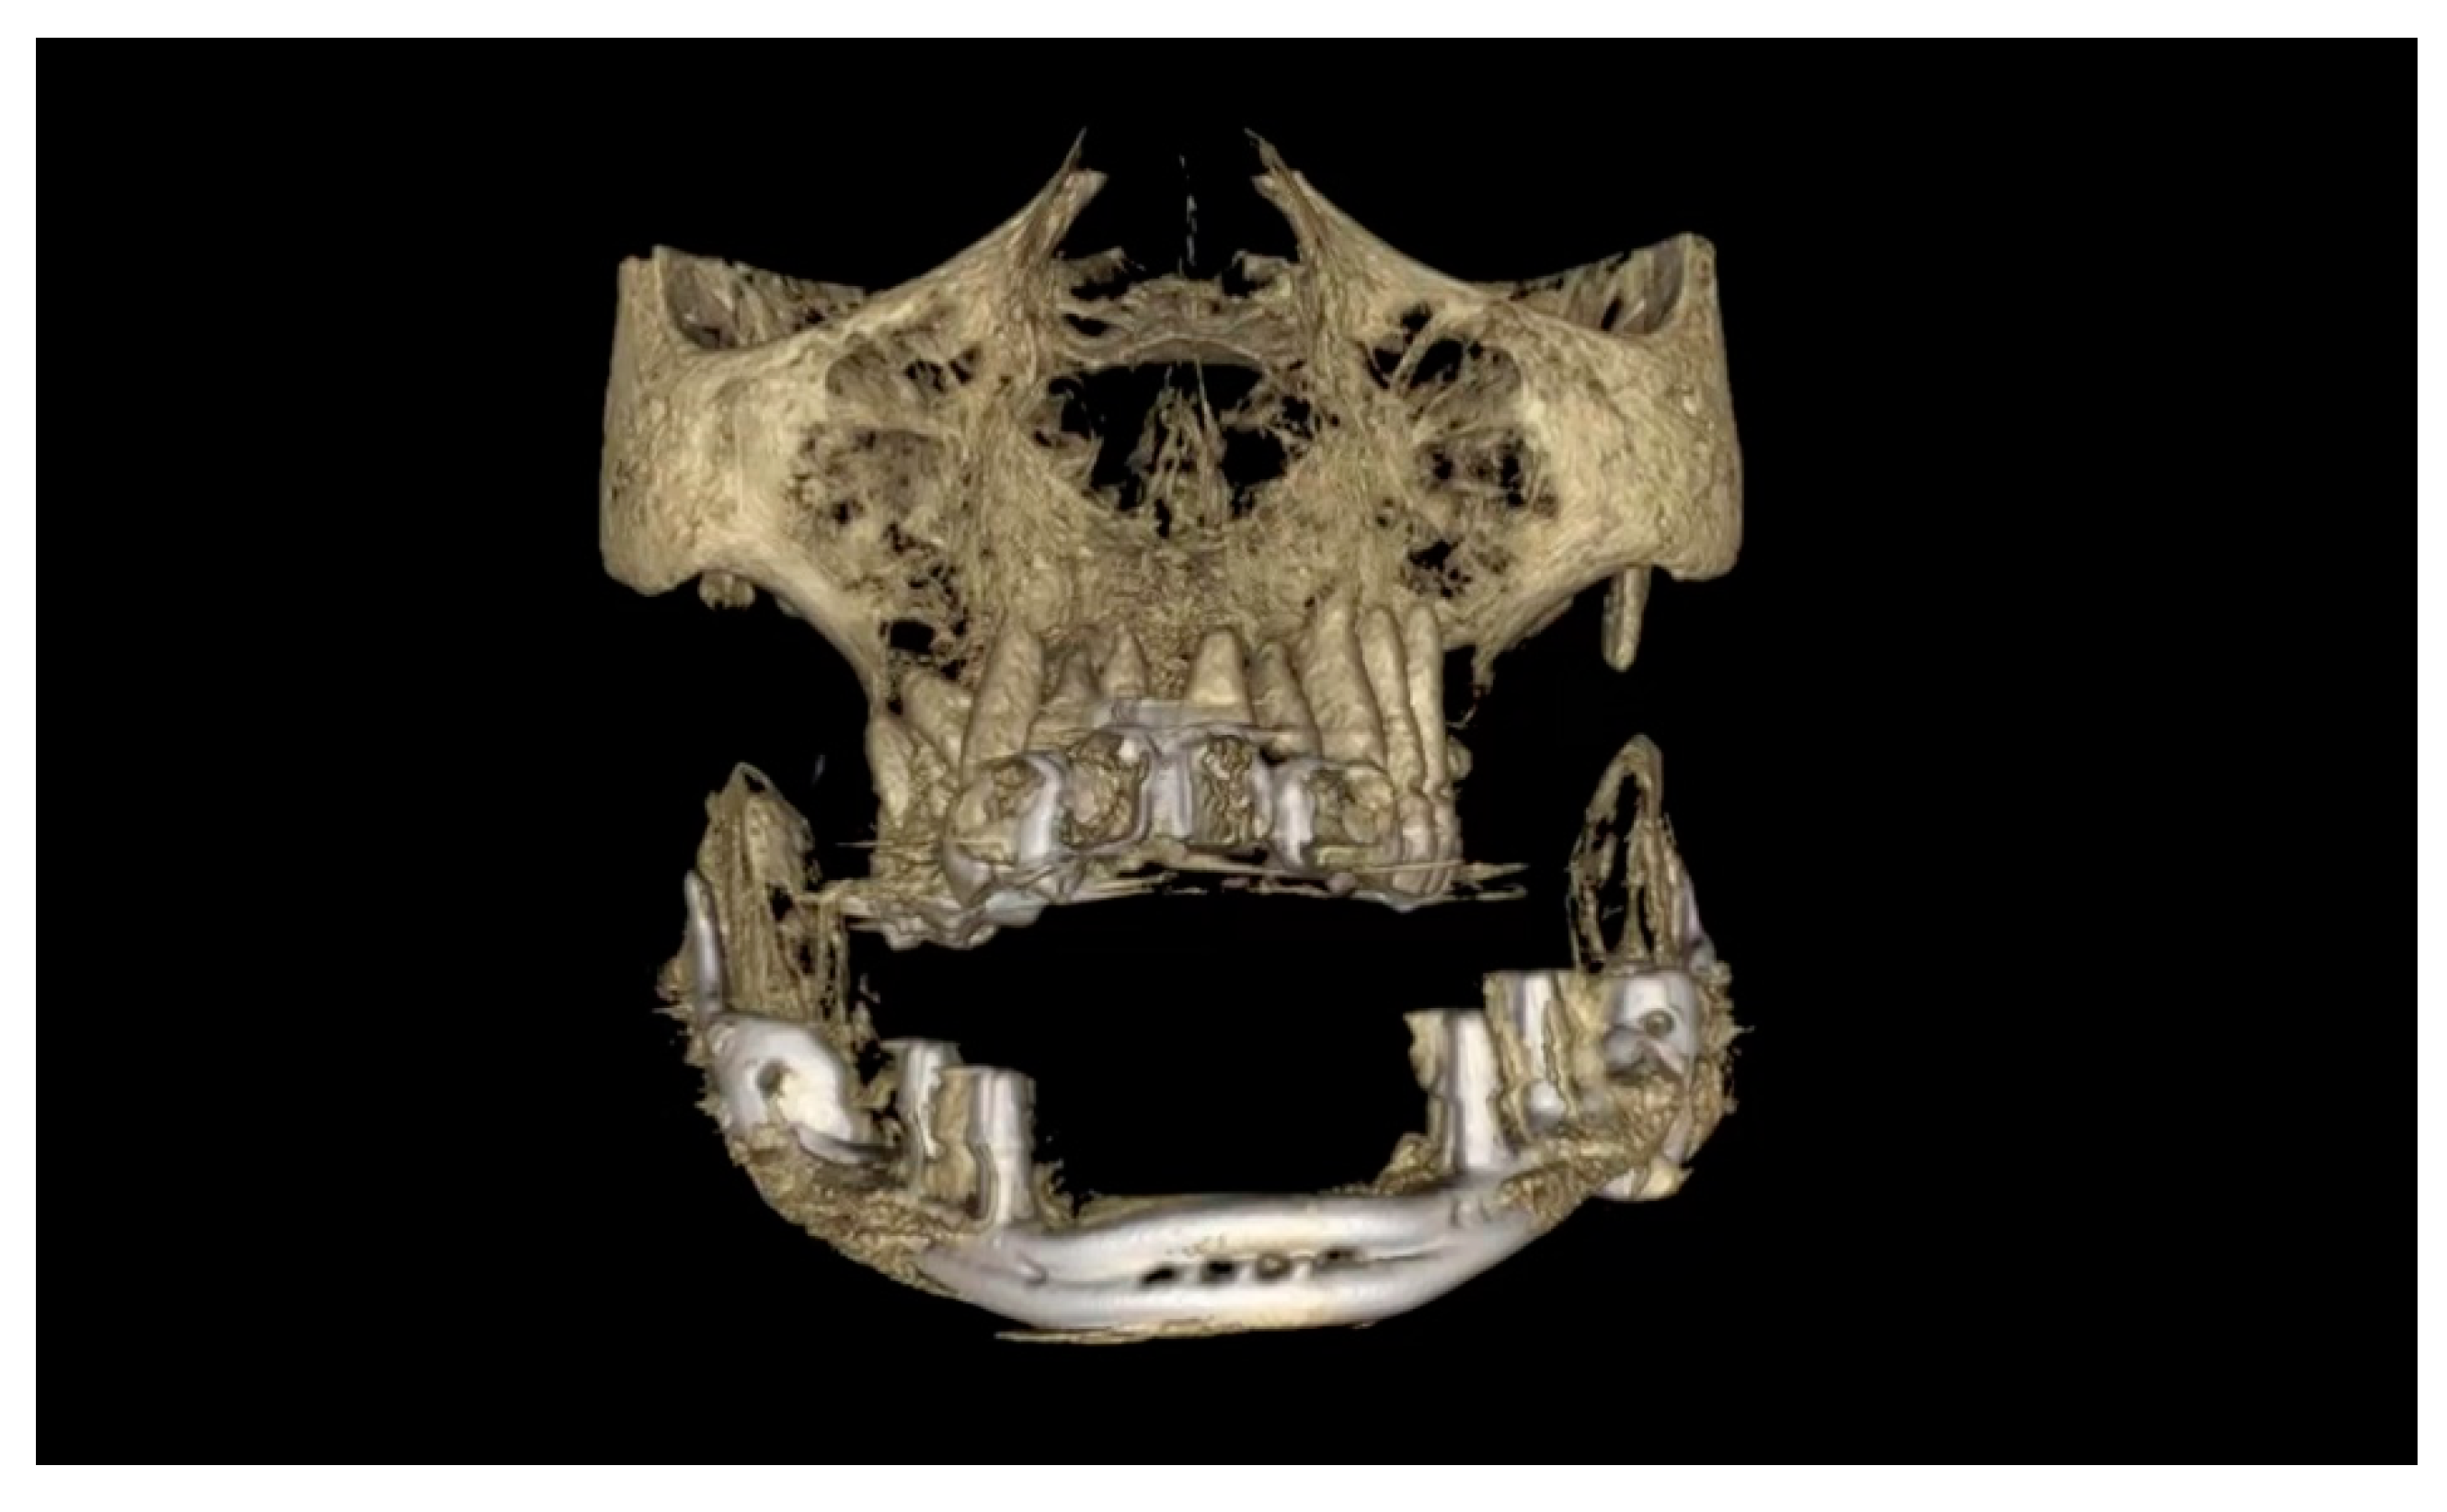

2. Case Presentation

2.5. Surgery

- The prosthesis reflected the original anatomy of the jaw.

- The prosthesis made it possible to suspend soft tissue by holes in the anterior portion.

- The prosthesis had the possibility of osteosynthesis by screws in the posterior portions.

- The jaw prosthesis placement and fixation was completed using screws (Tekka®, Pesaro, Italy) of 2 mm Ø and 7 to 9 mm length to attach them to the mandibular ramus.